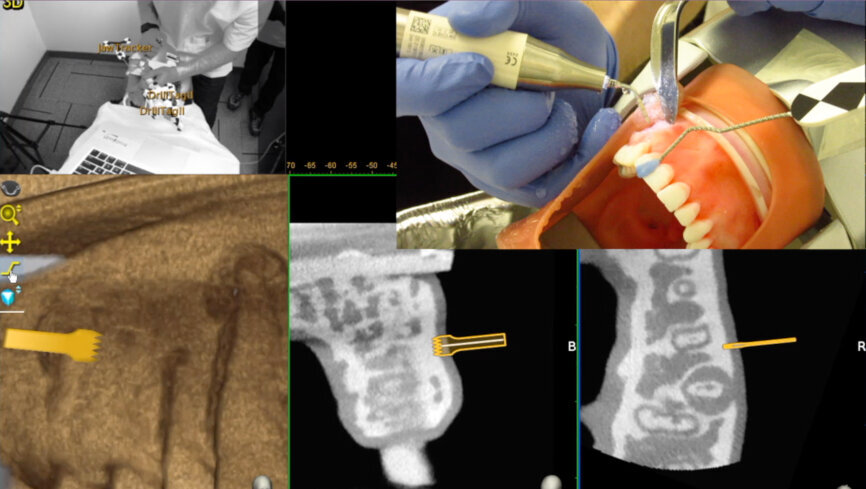

Fig. 2: An optical tracking sensor tracks the Jaw-Tracker, Tracer Tracker, Drill-Tracker and instrument.

Dynamic navigation facilitates real-time computer guidance technology using an imported CBCT data set. This is analogous to the use of GPS and satellite navigation. An innovative computer-guided technology, Trace and Place (TaP), has been developed by the Canadian company ClaroNav. TaP obviates the need for a fiducial stent, with the resultant increase in the accuracy of dentoosseous penetration. An optical tracking device (Fig. 2) tracks a Jaw-Tracker, the optical tracking tag connected to the patient’s jaw, and a Drill-Tag, which is the optical tracking tag connected to an instrument specific to the procedure. The tip is super imposed on the CBCT scan, which is mapped to the patient’s jaw.

The Jaw-Tracker (mandible or maxilla) or Head-Tracker (maxilla) is securely fastened to the jaw to be treated (Fig. 6). It should be noted that the Jaw-Tracker can be positioned at a distance from the rubber dam, unlike a Jaw-Tracker attached to a fiducial stent, which is more positionally restricted. Once the three landmarks have been determined, the optical tracking sensor tracks the Tracer- Tag/ Tracer- Tool as it is brushed around the landmarks on the facial, lingual and occlusal surfaces in a manner similar to applying etching or bonding solutions. The software shows the number of points contacted as a percentage (Fig. 7).